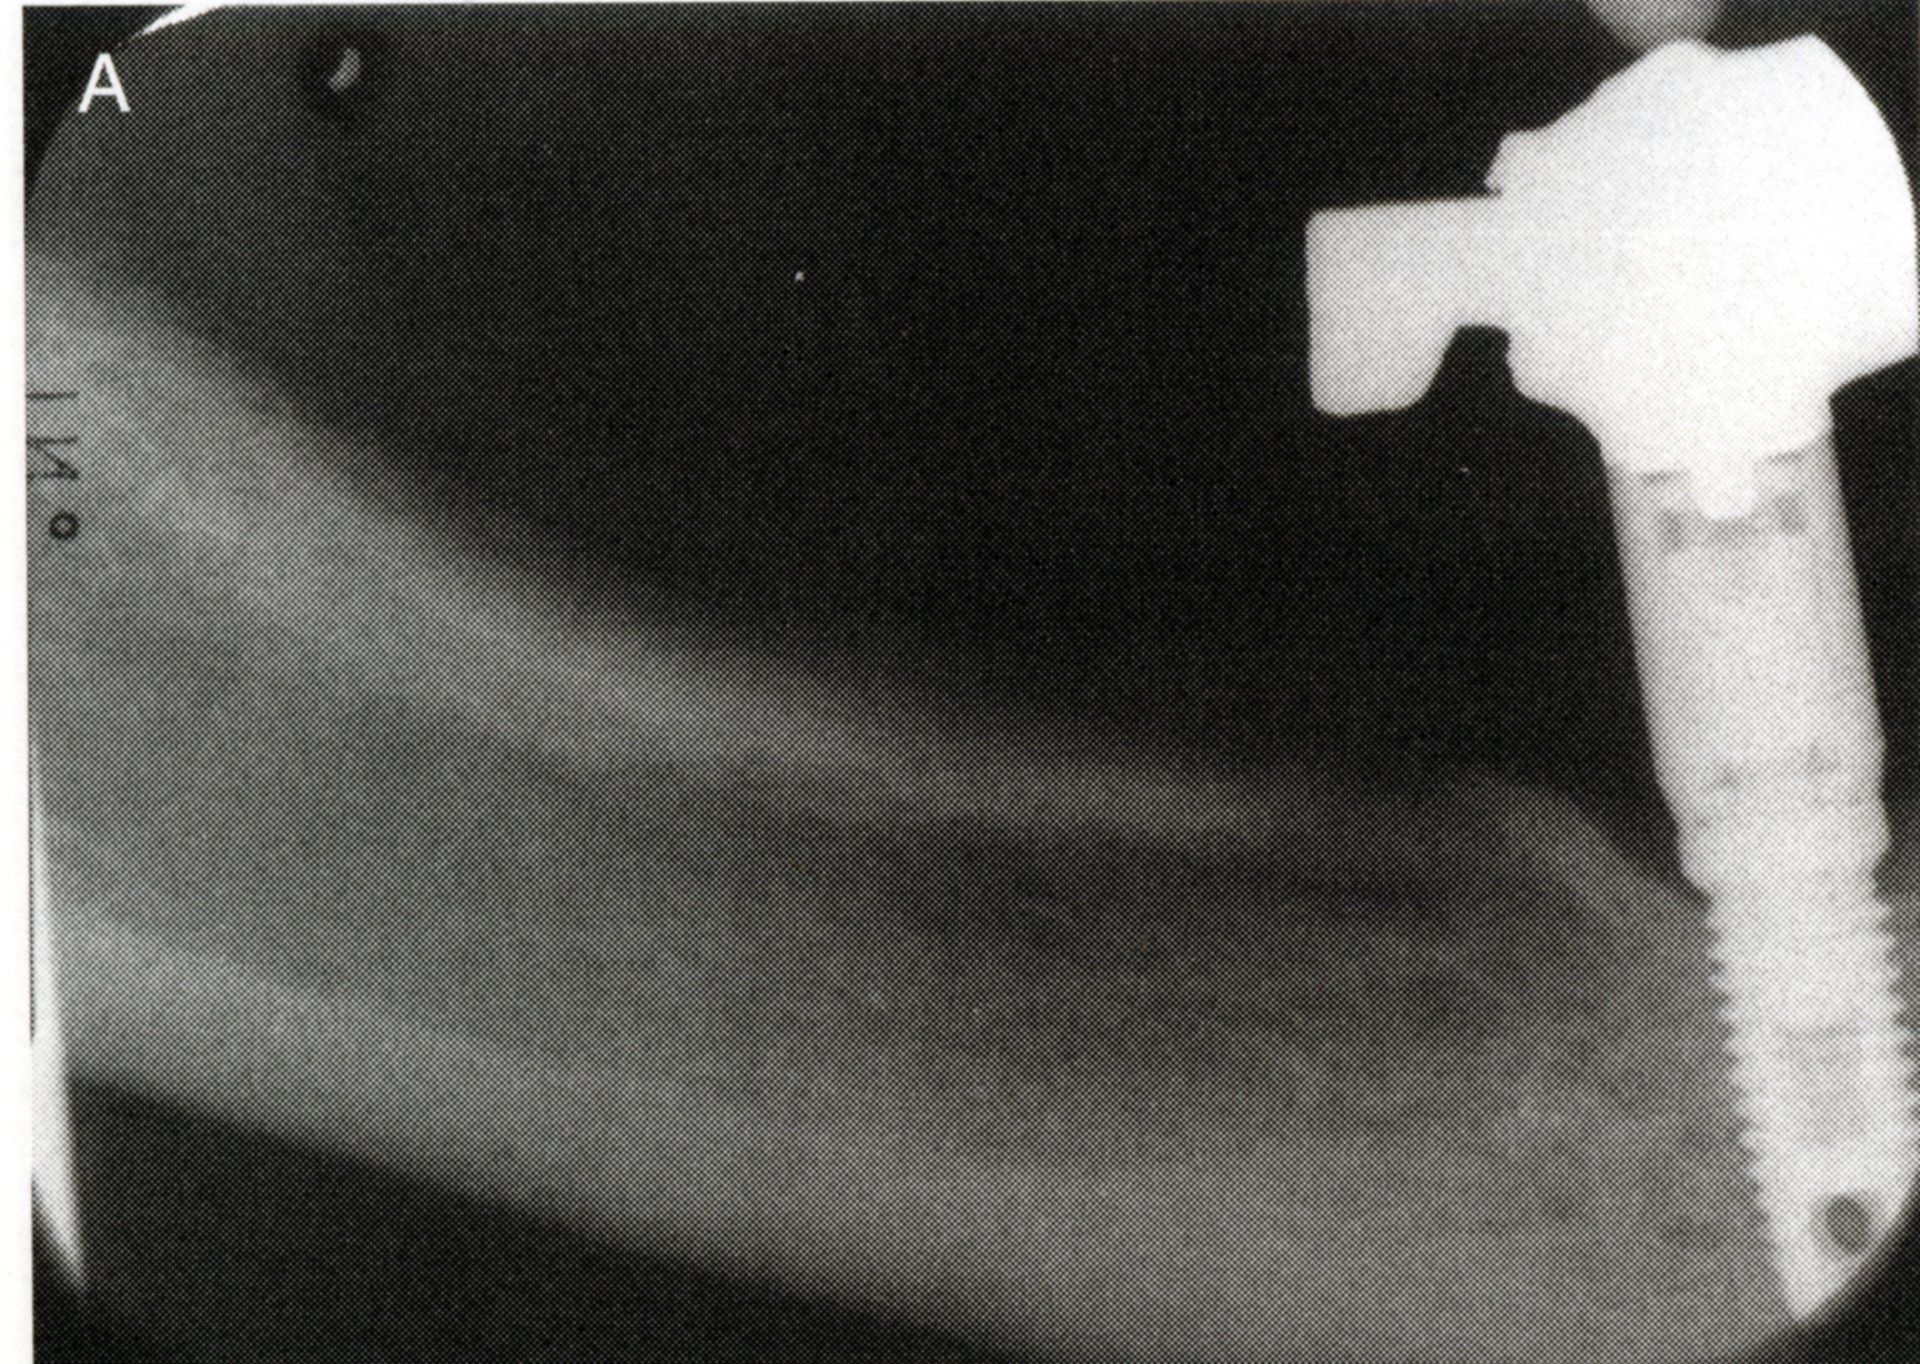

È necessario effettuare una visita che consentirà, in seguito a radiografie, calchi in gesso e fotografie, di effettuare nel dettaglio un’analisi preliminare del singolo paziente.

- il dentista inizia installando l’impianto, che è stato lasciato da tre a sei mesi a guarire e integrarsi con l’osso mascellare;

I principi della osseointegarzione secondo Branemark

L’osteointegrazione è il risultato di una osteogenesi da contatto che ha luogo su una superficie osteoconduttiva che permette l’adesione delle cellule ossee e l’organizzazione di queste nelle strutture degli osteoni. Questa guarigione del tessuto osseo è disturbata dalla colonizzazione microbica e dalla presenza di micromovimenti. Questi ultimi possono indurre cellule totipotenti a differenziarsi in fibroblasti piuttosto che in osteoblasti.